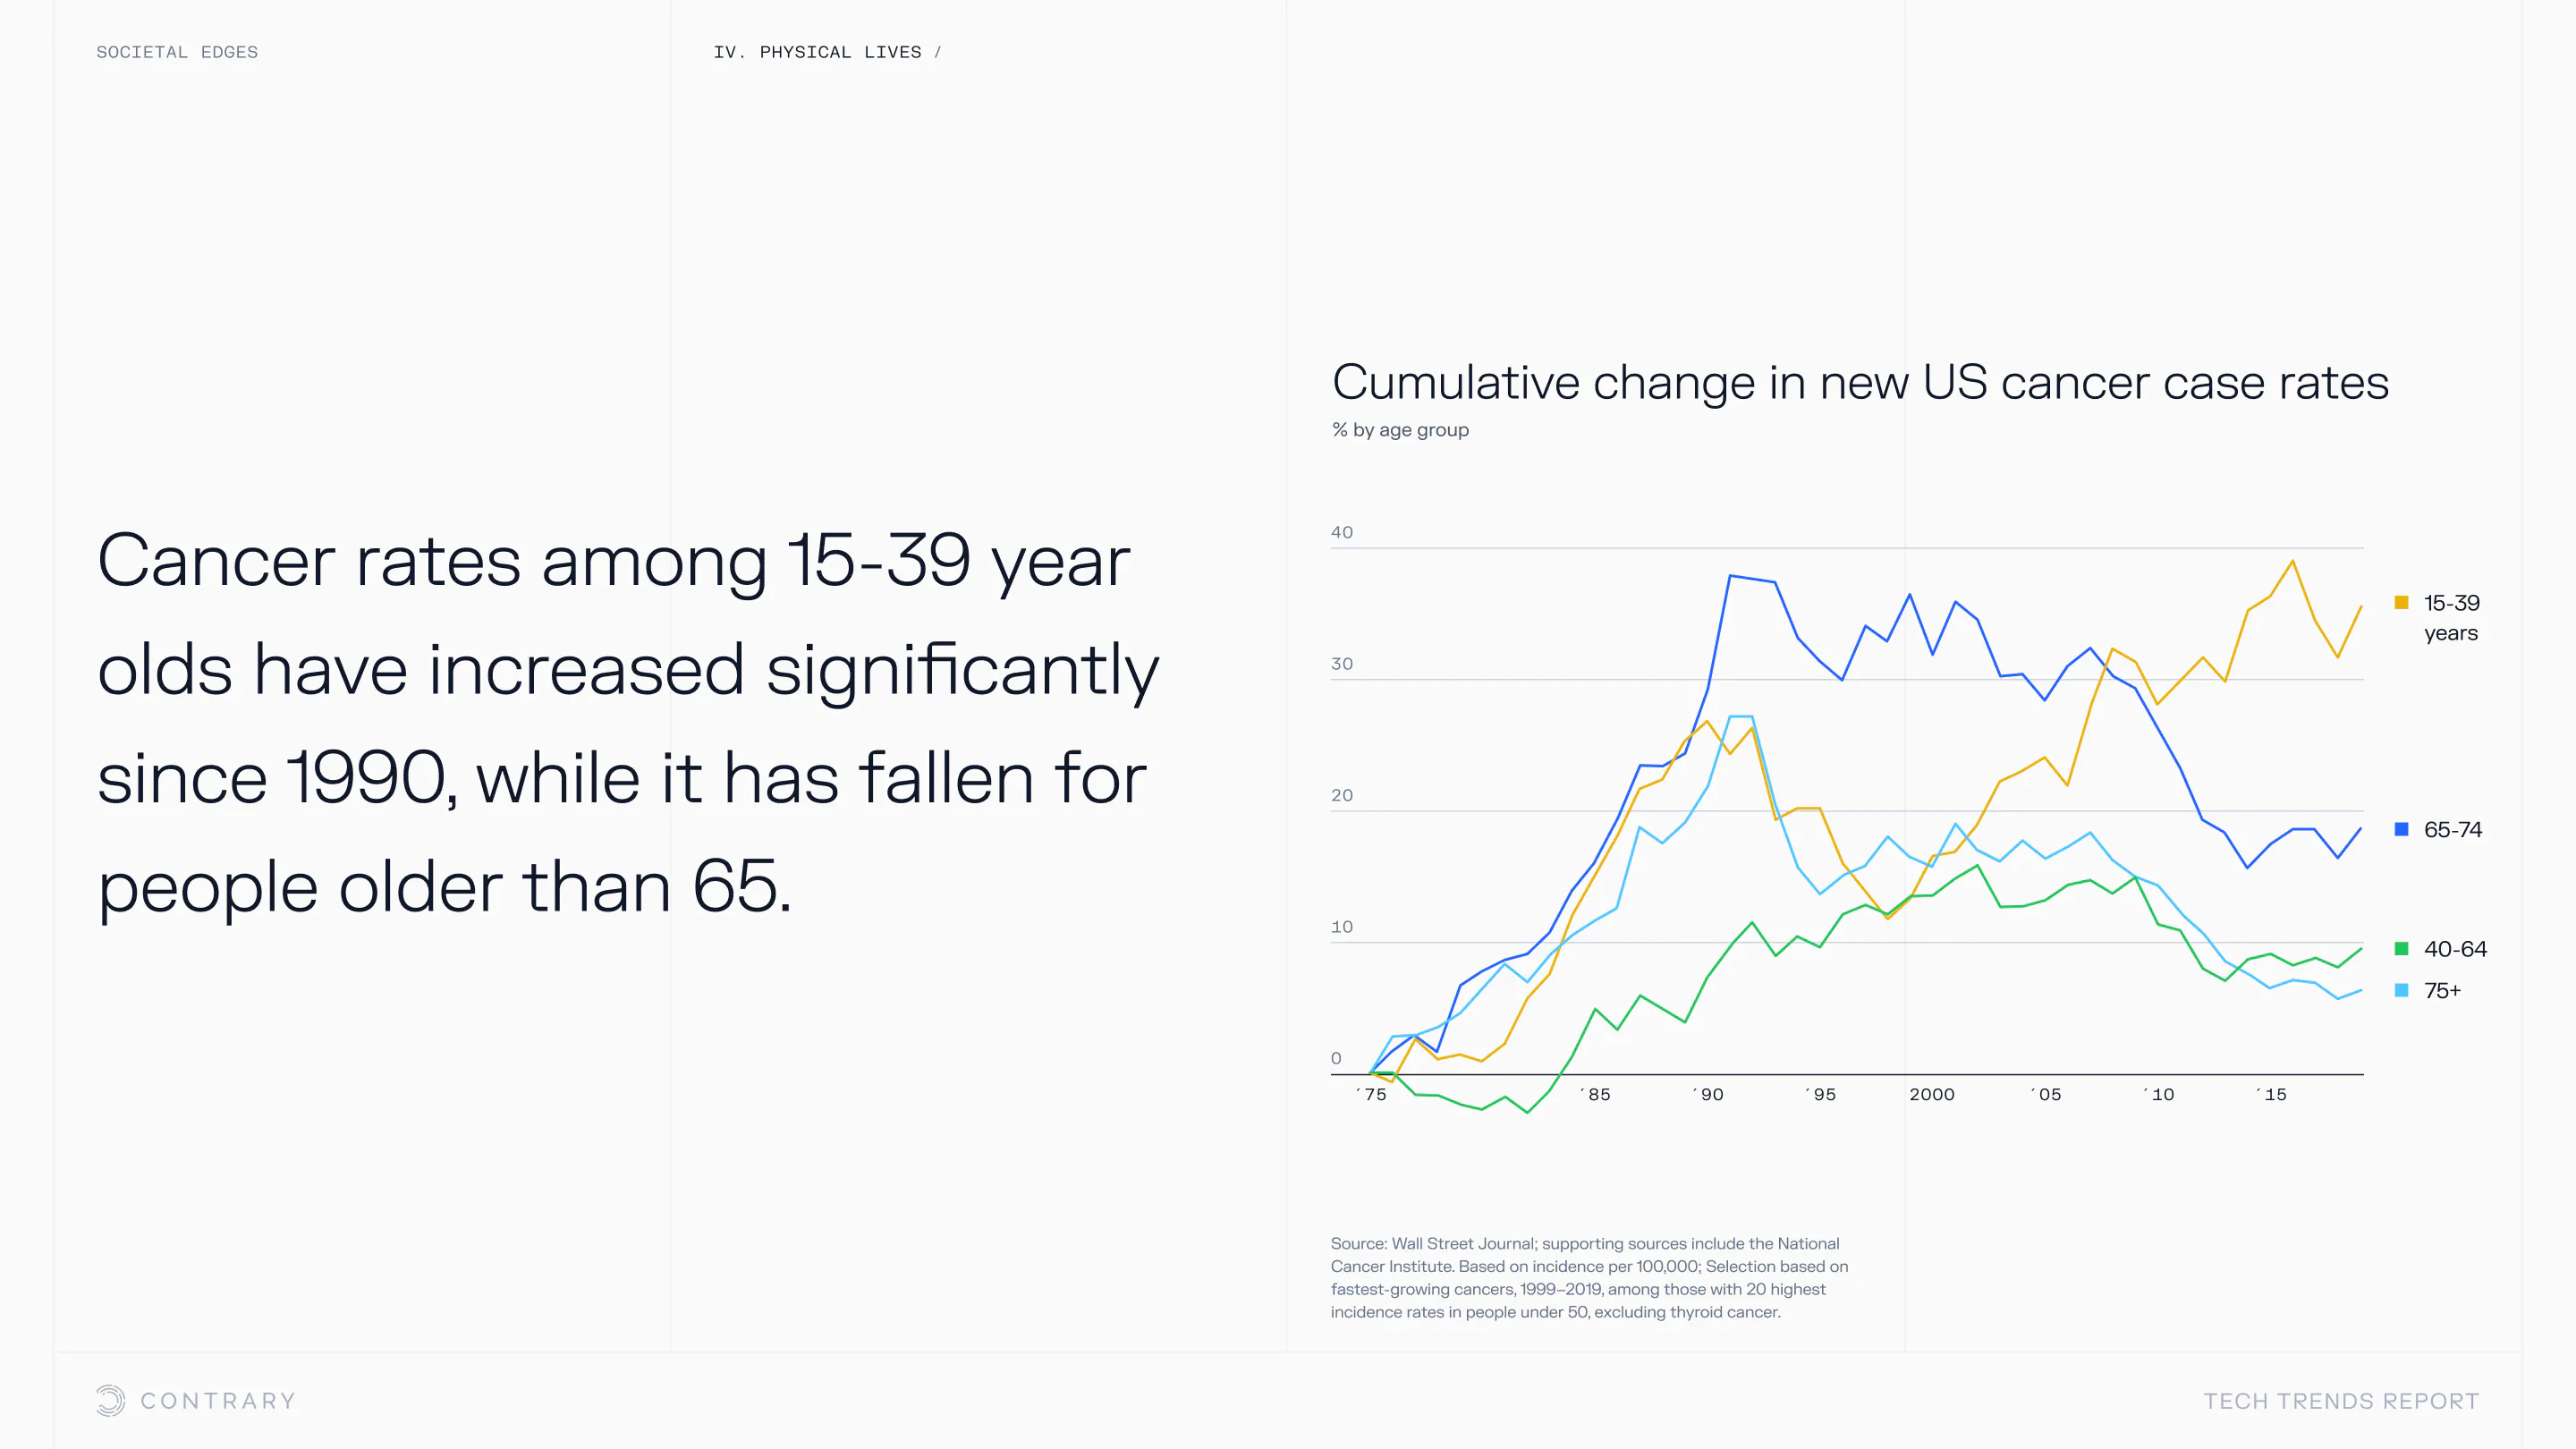

An aging population is bringing up a range of increased concerns, from mental health to disease control. Obesity and gastrointestinal cancers are plaguing younger generations. The cutting edge is tackling a system that has unhealthiness woven into it.